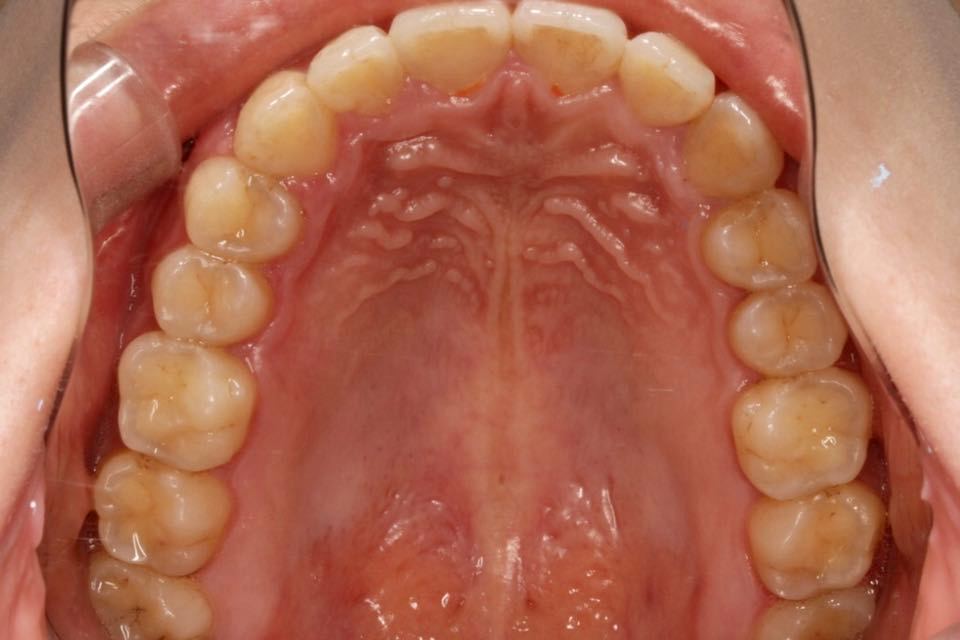

矫正前口内照:

口内:恒牙列,牙列拥挤(中度)。上下颌牙弓呈方圆型。左右对称。右侧磨牙近中性关系,左侧磨牙近中关系,右侧尖牙远中关系,左侧尖牙远牙中性关系。上颌中线偏右2mm,下中性居中。

上颌中线向患者左侧调整,上下颌中线对齐,扩弓加邻面去釉。